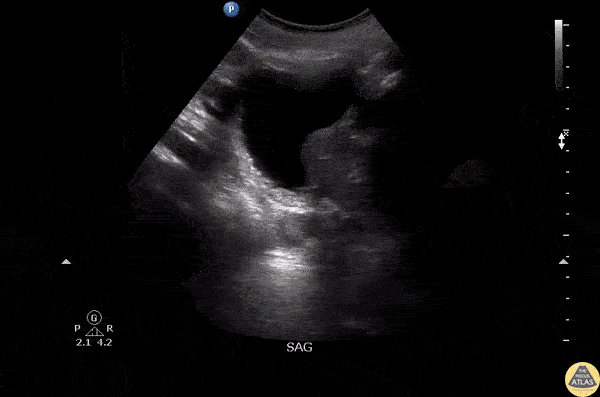

An elderly male presented with complaints of suprapubic pain. He recently had his foley catheter changed, which is draining but with significant pain. Sagittal view of the pelvis revealed the foley balloon inflated within the prostatic urethra. Image courtesy of Robert Jones DO, FACEP @RJonesSonoEM Director, Emergency Ultrasound; MetroHealth Medical Center; Professor, Case Western Reserve Medical School, Cleveland, OH View his original post here